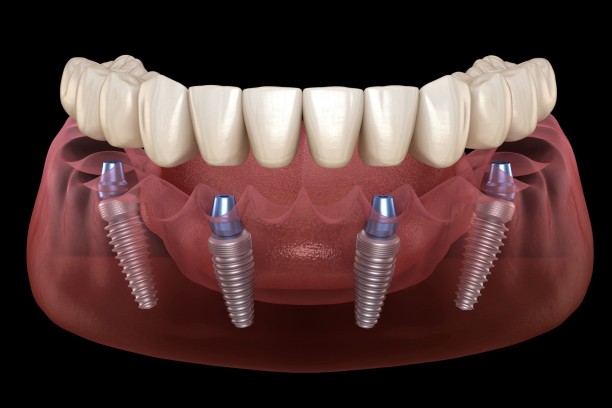

All-on-4 Implants

Full-arch restoration using just 4 implants, often completed in a few days.